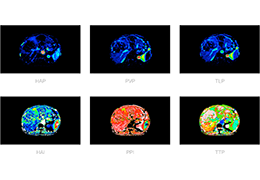

ART-Plan™ Artificial Intelligence Contouring